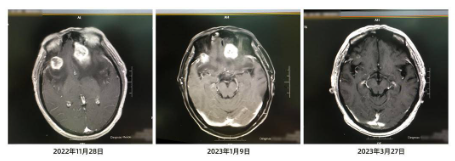

四期治療后,3月27日,鄧先生頭顱MR平掃,發(fā)現(xiàn)其右側(cè)額葉見一個(gè)環(huán)形顯著強(qiáng)化影,長徑約0.65cm。這與1月9日在進(jìn)行“免疫+化療+抗血管生成藥”聯(lián)合用藥治療之前相比,病灶明顯縮小,達(dá)到部分緩解。

朱主任告訴記者,臨床上,肺癌腦轉(zhuǎn)移的患者實(shí)現(xiàn)部分緩解是比較少見的。同時(shí),朱主任還特別強(qiáng)調(diào),抗癌是一場持久戰(zhàn),不僅需要合理有效的治療手段,也需要患者積極樂觀的心態(tài)。